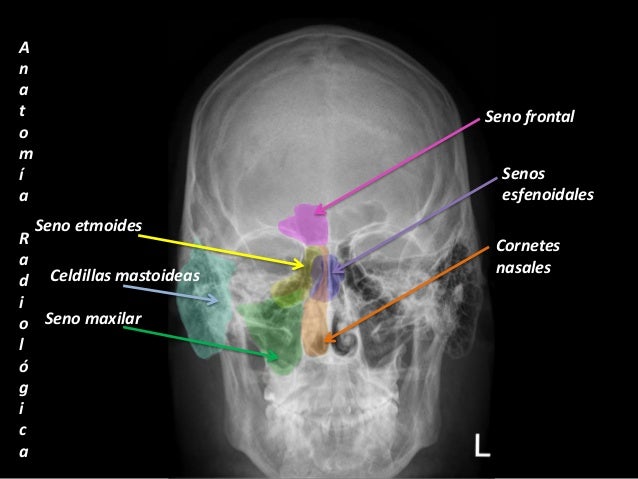

Forma parte de serie radiográfica para evaluación de senos paranasales, junto a RX Caldwell y lateral de cráneo 4 La proyección de water es muy útil para estudiar el piso de la órbita, reborde orbitario inferior, hueso malar y senos maxilares 5. El hueso de la parte superior del brazo se conoce como húmero Los dos huesos en el antebrazo (abajo del codo) se conocen como radio y cúbito Si niño pudo haber sufrido una fractura de brazo debido a un accidente de automóvil, mientras juega deportes, o a una caída con el brazo extendido Si el brazo de su niño esta torcido o sufre un. 12hueso wormiano 13atlas 14arco posterior atlas 15axis 16hueso hioides 17hueso mandibular 18canal mandibular 19paladar duro paladar blando 21Úvula 22concha nasal inferior 23concha nasal superior 24apÓfisis malar 25apÓfisis piramidal 26seno maxilar 27apÓfisis alveolar del maxilar 28apÓfisis estiloides.

Hueso malar El hueso cigomático (también conocido como el malar) es uno de los huesos formados más irregulares del cráneo Consta de tres procesos diferentes, variando en tamaño y forma Debido a que el par de ellos sobresalen lateralmente y forman las eminencias de la cara ( “pómulos “), ambos son propensos a fracturas. Radiografía que permite la evaluación de senos paranasales, junto a RX Caldwell y lateral de cráneo Se utiliza para confirmar sinusitis, delinear fracturas del hueso malar y, en general, para ver el macizo cráneo facial. También existen técnicas como la de Malar o Waters donde se utilizan posiciones intermedias (semiaxiales) Cuál es la característica que tienen que decir para determinar si esta Rx está bien o no?.

Huesos del cráneo Hueso frontal El hueso frontal (os frontale PNA) es un hueso del cráneo humano Es un hueso plano, impar, central, simétrico con 7 Páginas • 565 Visualizaciones Huesos Del Craneo HUESOS DEL CRÁNEO El cráneo es una caja ósea que contiene y protege al cerebro, el cerebelo, el tallo cerebral y los órganos de la. Muy útil para estudiar el suelo de la órbita, reborde orbitario inferior, hueso malar y senos maxilares Es casi obligada para el estudio de las fracturas del suelo de la órbita, maxilares, malar y arco cigomático RX de Extremidad AP LAT 1 Región RX de Fluoroscopia RX de Histerosalpinograma RX de Hombro Derecho 2 Proyecciones RX. Primero el hueso nasal y el proceso frontal del hueso maxilar Para comprobar el nivel del seno maxilar, se puede probar con el “Nivel.